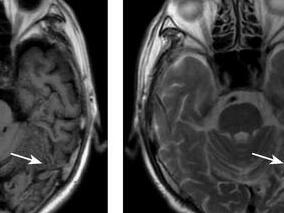

1小时条评论1 病例简介 患者男,74岁,右利手,退休人员,受正式教育15年。患者于2010年6月21日无明显诱因出现心悸、气促,就诊于当地卫生院,诊断为心房颤动,予对症治疗。2010年6月22日晚患者突然出现不认识家人、语言表达障碍、性格改变,伴头晕,无头痛、无恶心呕吐、无四...